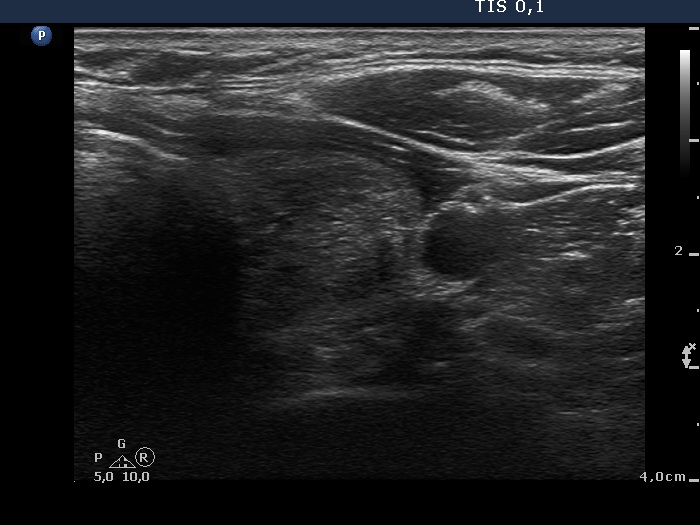

Benign hyperplastic nodules (histological diagnosis) - case cons 024 |

The larger lesion has a solitary bright figure which shape stands for a comet-tail artifact.